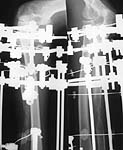

Since Dec 2001 the patient has been managed in our institute. Jan 2002 the plate was removed, resection of bone ends and osteotomy of the distal fragment were performed. Then gradual traction started 0,5 mm/day, with 10-15 day pauses. The temp was decreased to 0.25 mm/day due to poor regenerate response and distraction finished at July 2002 (image left).

Recent film, Dec 2002 (image right) shows lysis of bone ends and slow maturing of the regenerate.